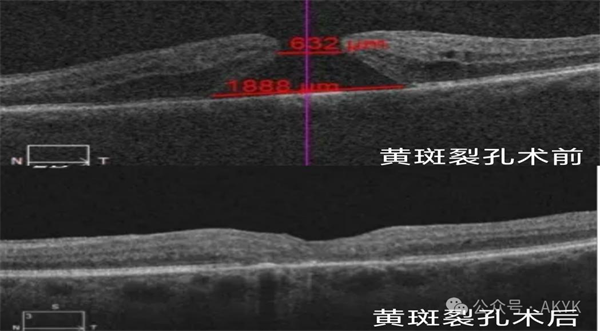

新業(yè)務(wù)二

復(fù)雜黃斑裂孔修復(fù)術(shù):修補(bǔ)裂孔提升視力,降低致盲率。